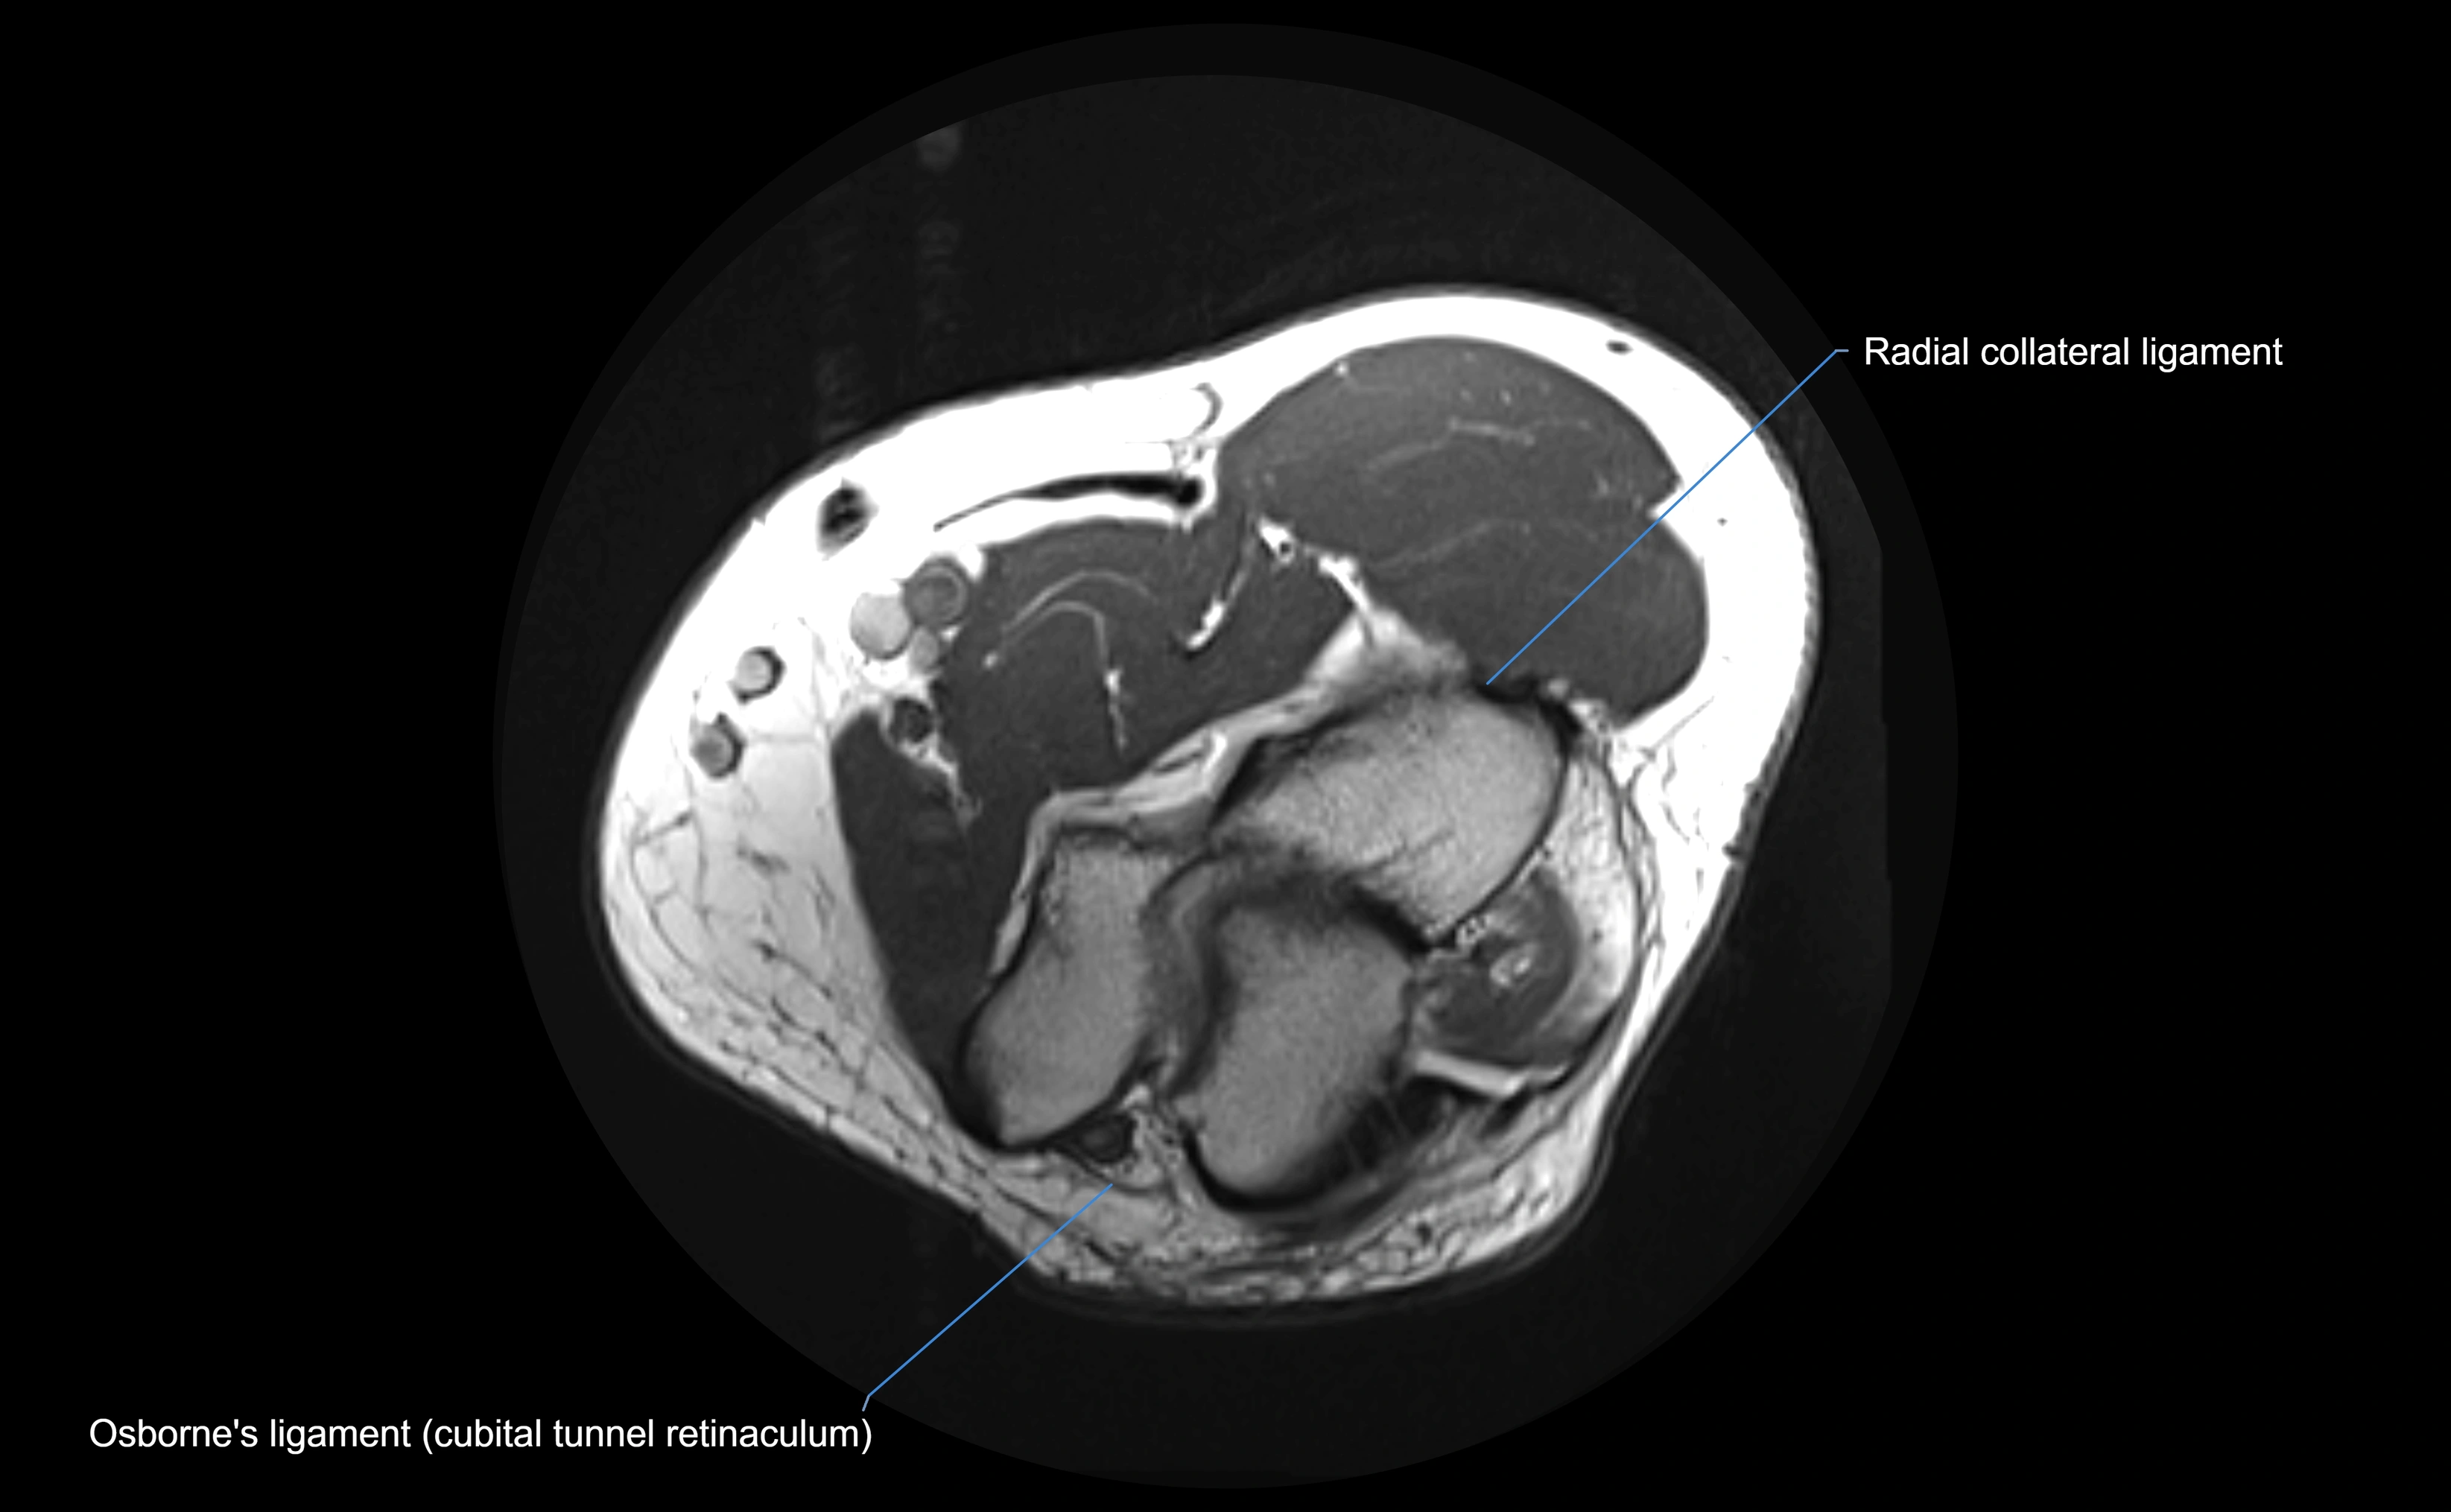

MRI Appearance

T1-weighted images:

• Ligament: low signal intensity (dark), appearing as a continuous band around the radial head.

• Adjacent fat and marrow: bright, creating contrast with the ligament.

• Thickening or disruption indicates injury or fibrosis.

• Joint capsule and synovium seen as thin low-signal lines contiguous with ligament margins.

T2-weighted images:

• Ligament: low signal (dark) with clear delineation from joint fluid.

• Fluid or edema: bright hyperintense, separating or surrounding the ligament in partial tears.

• Complete tear: discontinuity or non-visualization of ligament fibers, often with joint effusion.

Proton Density Fat-Saturated (PD FS):

• Normal: dark, well-defined band outlining the radial head.

• Partial tear: irregular or bright hyperintense signal within or adjacent to ligament fibers.

• Joint effusion and reactive synovitis appear bright and are well visualized.

MRI images

image